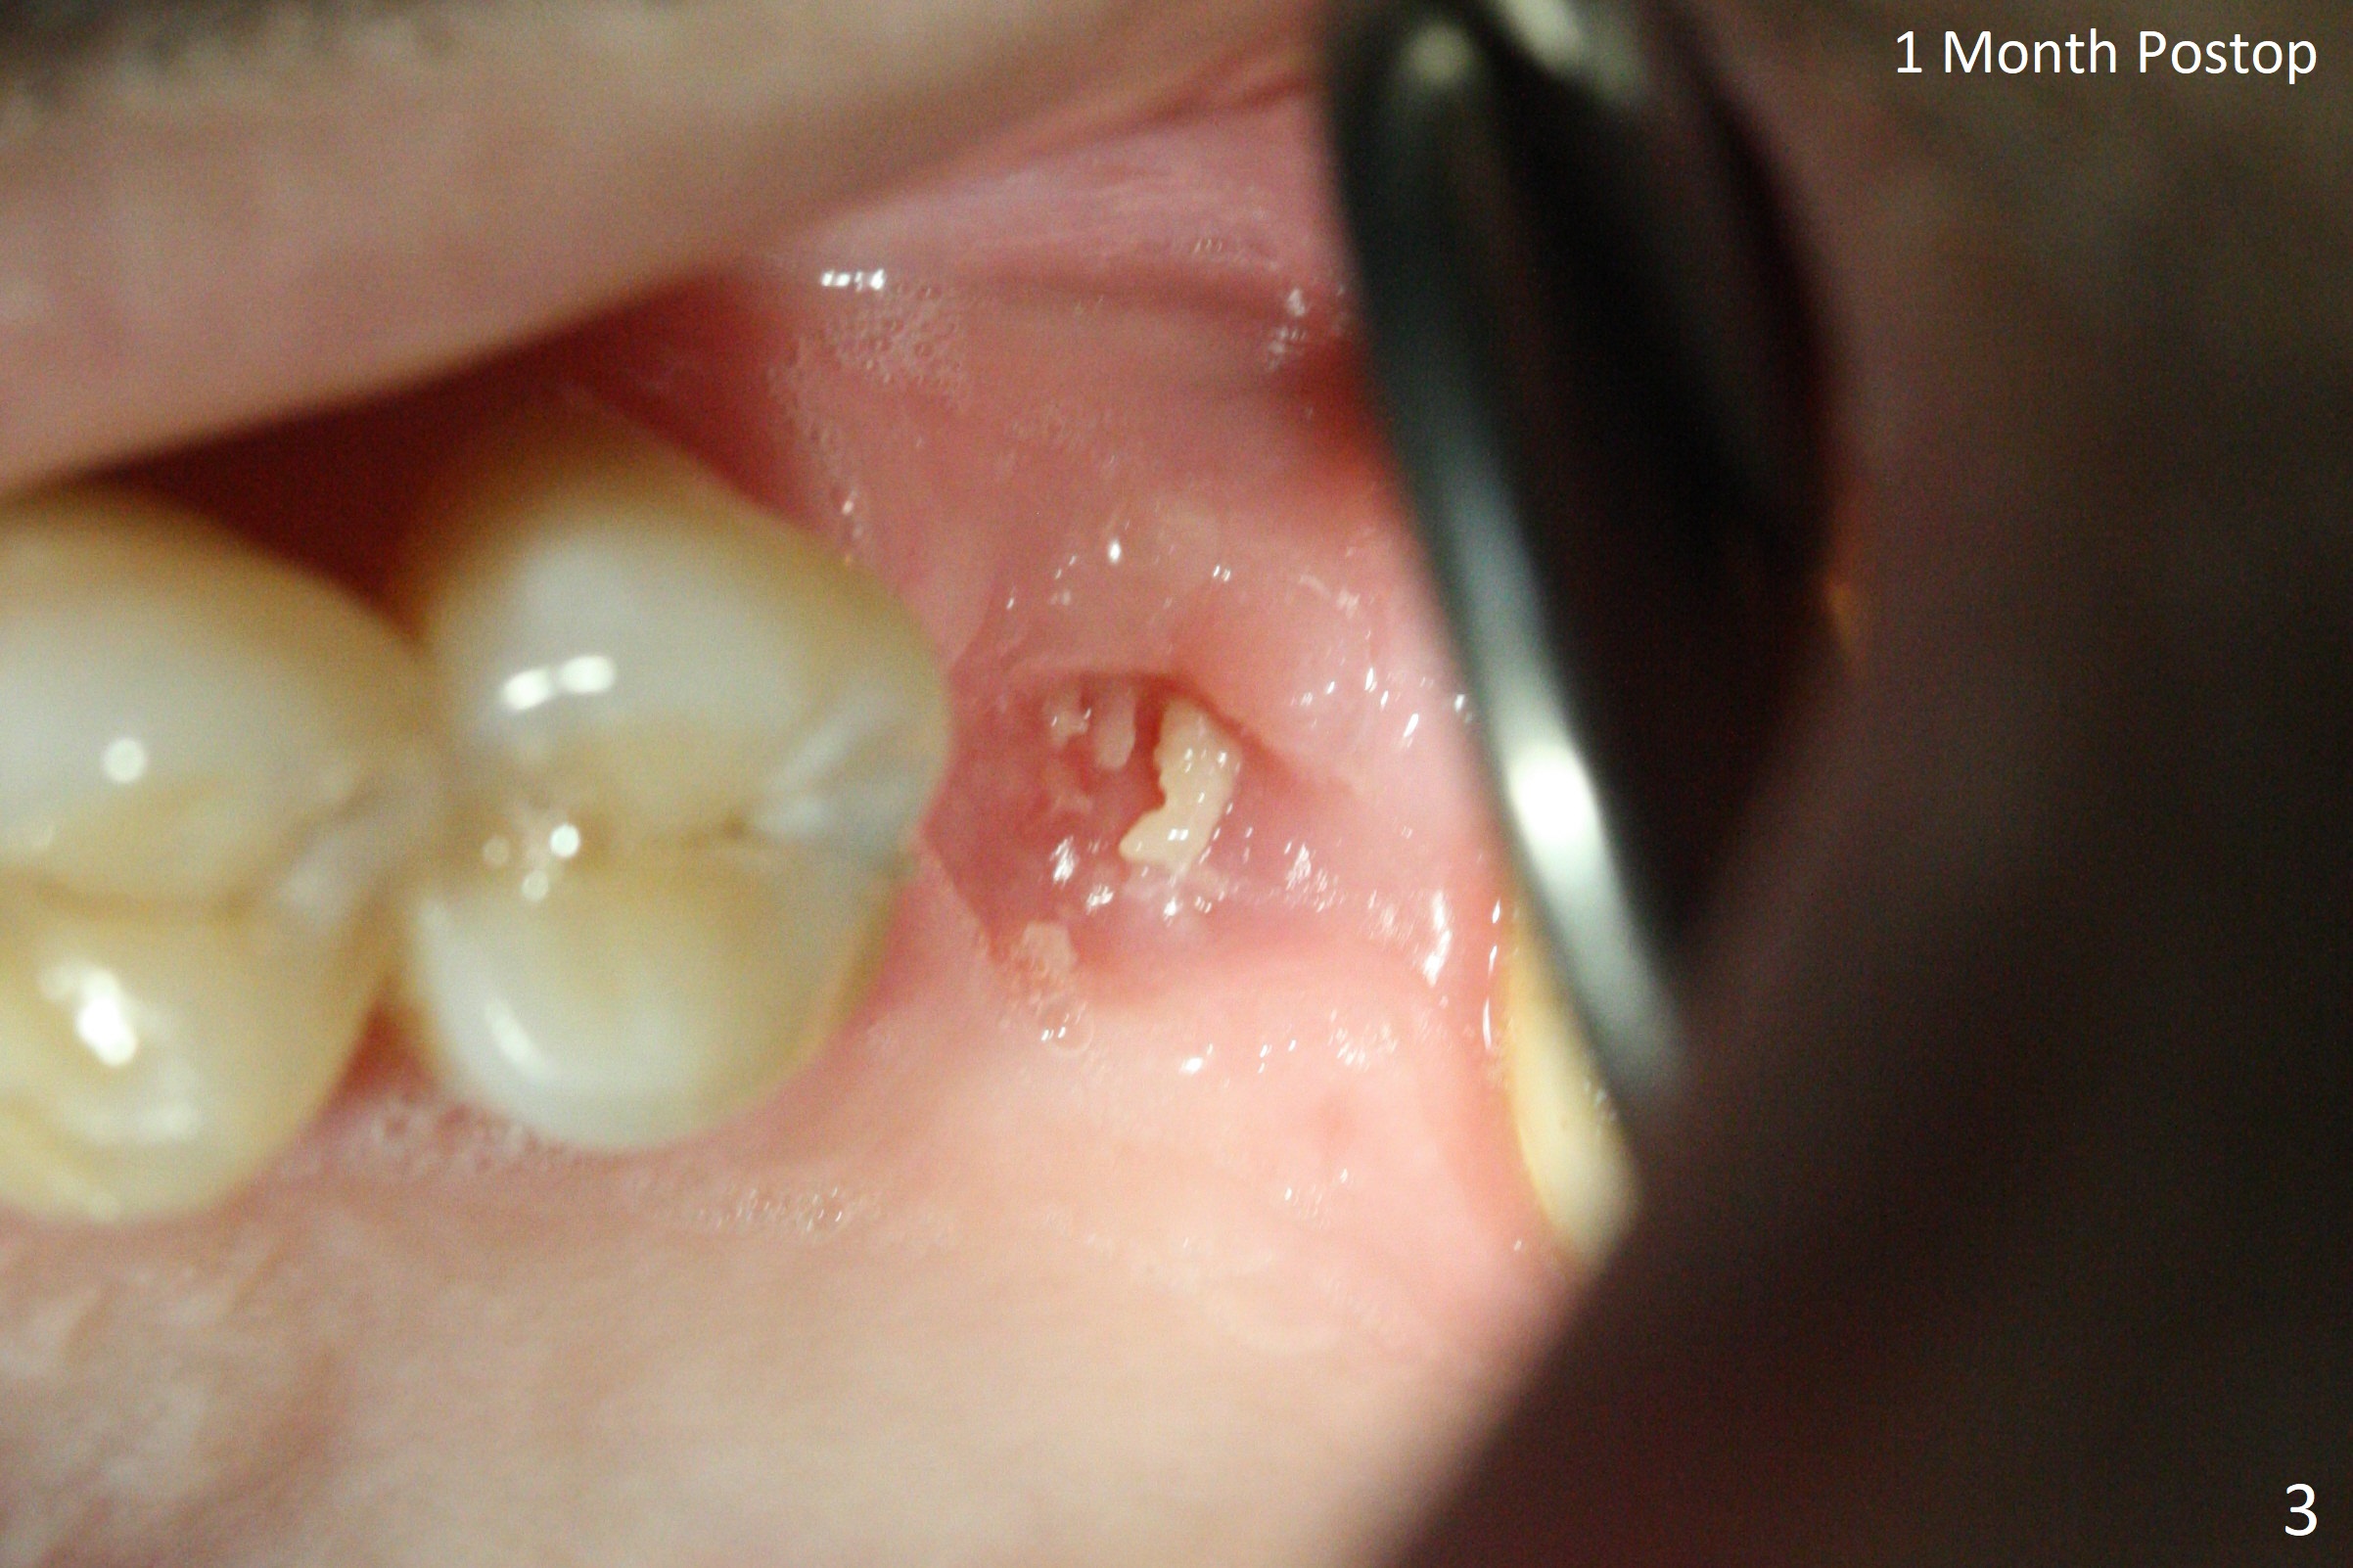

When the crown and abutment at #14 are removed, the implant is found to be shallowly placed. Upon incision, the implant threads are exposed circumferentially and coronal to the buccal crest (Fig.1 *). It seems to be difficult to expect bone regeneration post bone graft. The implant (6.4x6 mm) is removed with a 7/8 mm trephine bur, followed by sticky allograft (Fig.2 *), PRF membrane and 6-month membrane. In spite of the setback, the bone height increases from 3.9 mm to 11 mm due to sinus lift associated with the previous implant placement (Fig.2 L). The depth of the 2nd placement will be controlled by surgical guide. When the periodontal dressing dislodges 11 days postop, the 6-month membrane is lost as well as part of the bone graft. If there is remaining apical native bone, an immediate implant should be placed so that bone graft can be kept in place more securely with an immediate abutment and provisional! The seemingly conservative approach is actually not safe. The wound heals 1 month postop (following dislodgement of the 2nd periodontal dressing, Fig.3). Three months later, consider using bone expanders to do sinus lift and place a SM implant subcrestal. Take PA after 1st expander to the depth. The wound heals 4 months postop (Fig.4), but the bone height (Fig.5) and width (Fig.6) decreases. The latter continues to decrease 9 months postop (Fig.7,8), but bone density is high, average 1360 units. Preparation includes guide, incision, sinus lift, implant placement (possibly tissue-level (9) or FC if the sinus membrane perforates), bone graft, and suture.